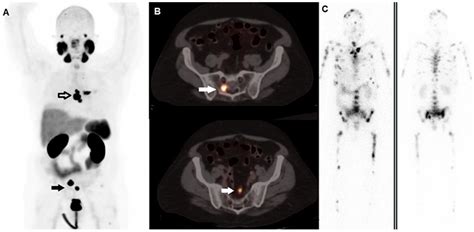

Why Physicians Prefer MRI Over Traditional Biopsy

Historically, a prostate biopsy was the initial step following an elevated Prostate-Specific Antigen (PSA) test. However, "blind" biopsies can often miss tumors located in the anterior or harder-to-reach areas of the prostate. Incorporating an MRI for prostate cancer before a biopsy allows for a "targeted" approach. Known as an MRI-fusion biopsy, this technique overlays the MRI images onto real-time ultrasound guidance, ensuring that the needle is directed precisely at the suspicious tissue identified on the scan.

Long-Term Monitoring and Surveillance

One of the most significant advancements facilitated by MRI for prostate cancer is the shift toward "Active Surveillance." Many prostate cancers are slow-growing and may never cause symptoms or shorten a patient's life. Instead of jumping straight to surgery or radiation, which carry risks of erectile dysfunction and incontinence, many men choose to monitor their condition. Periodic MRI scans allow physicians to track the size and appearance of lesions over months or years, ensuring that if a tumor shows signs of aggressive growth, intervention can occur at the most effective time.